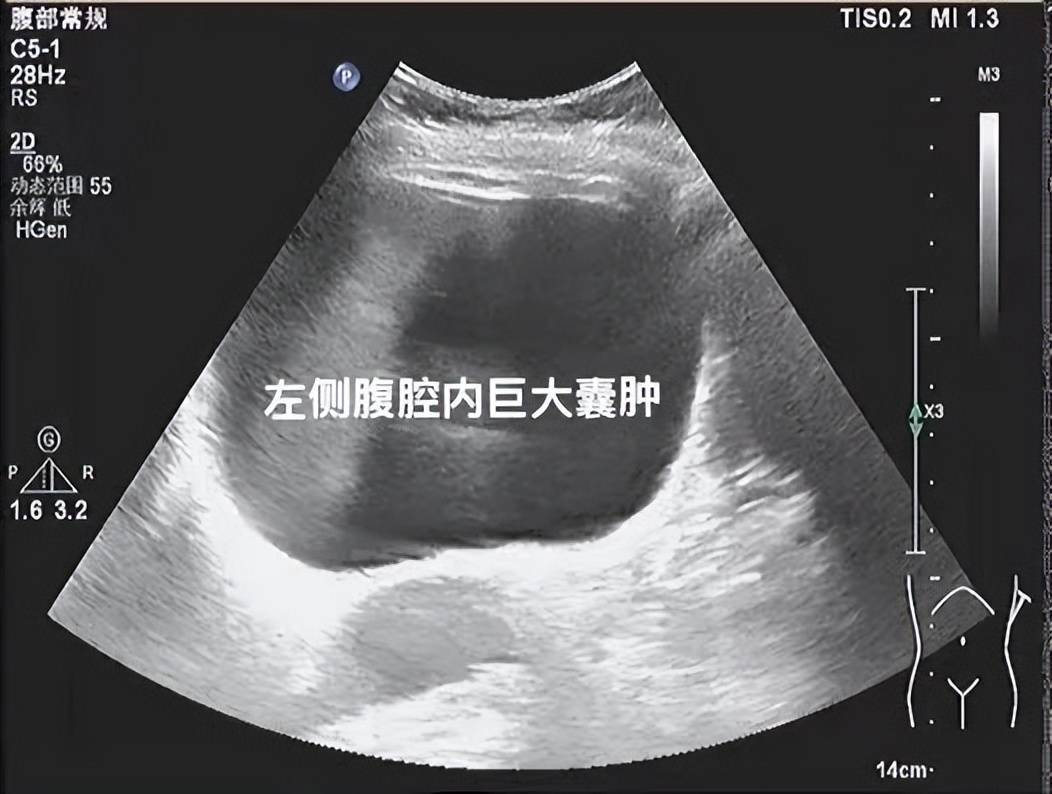

脾囊肿超声图片

脾脏囊肿?梗死?